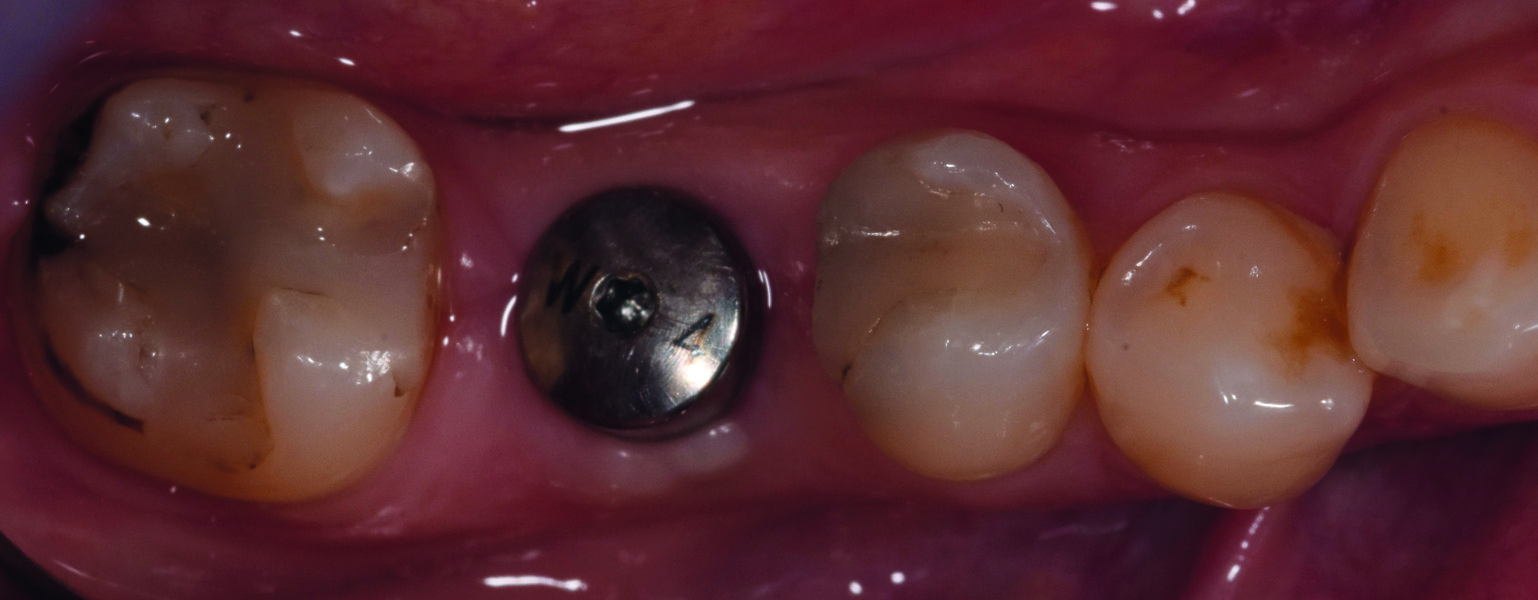

Trois mois plus tard. Second temps du protocole en deux temps. Légère incision crestale, dépose de la vis de couverture et ensuite mise en place de la vis de cicatrisation (Fig. 14).

Fig. 14 : Vue occlusale du pilier de cicatrisation vissé dans le col implantaire.